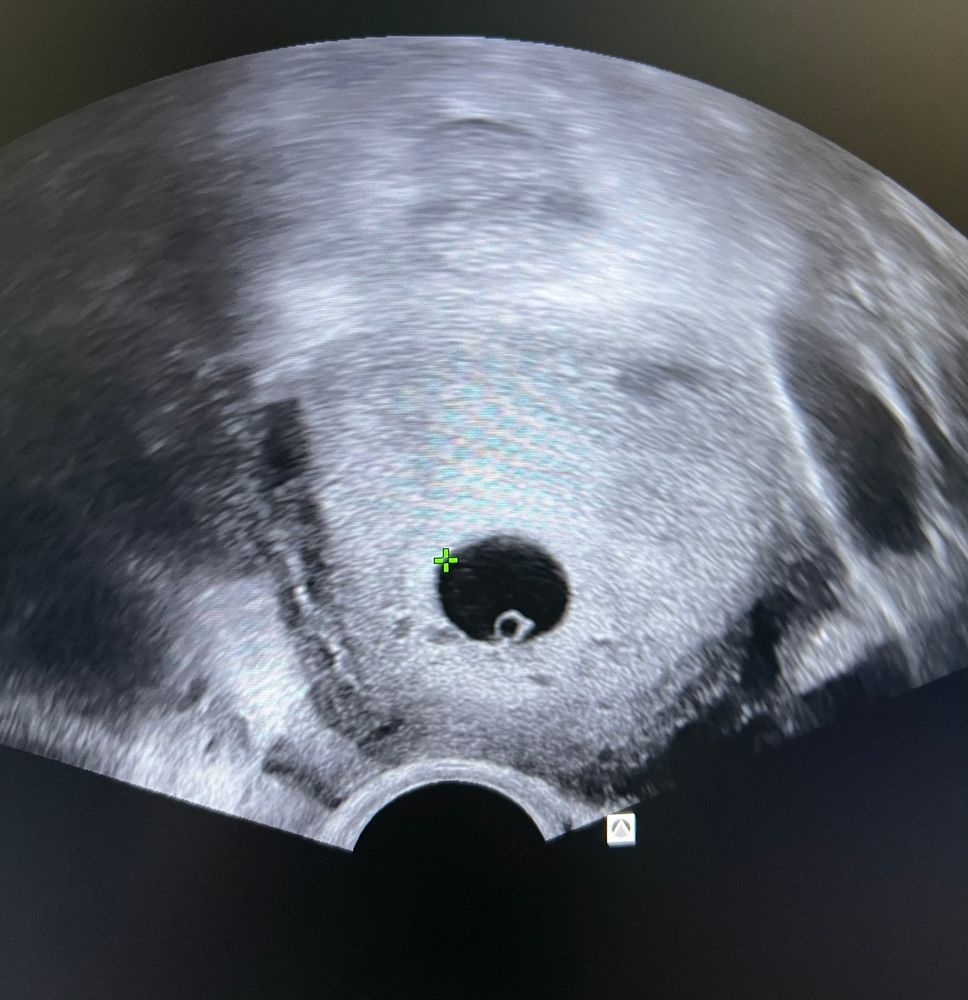

20 дпп. Первое узи

УЗИ 35дпп поставили срок 8,2 недели Наша история ЭКО